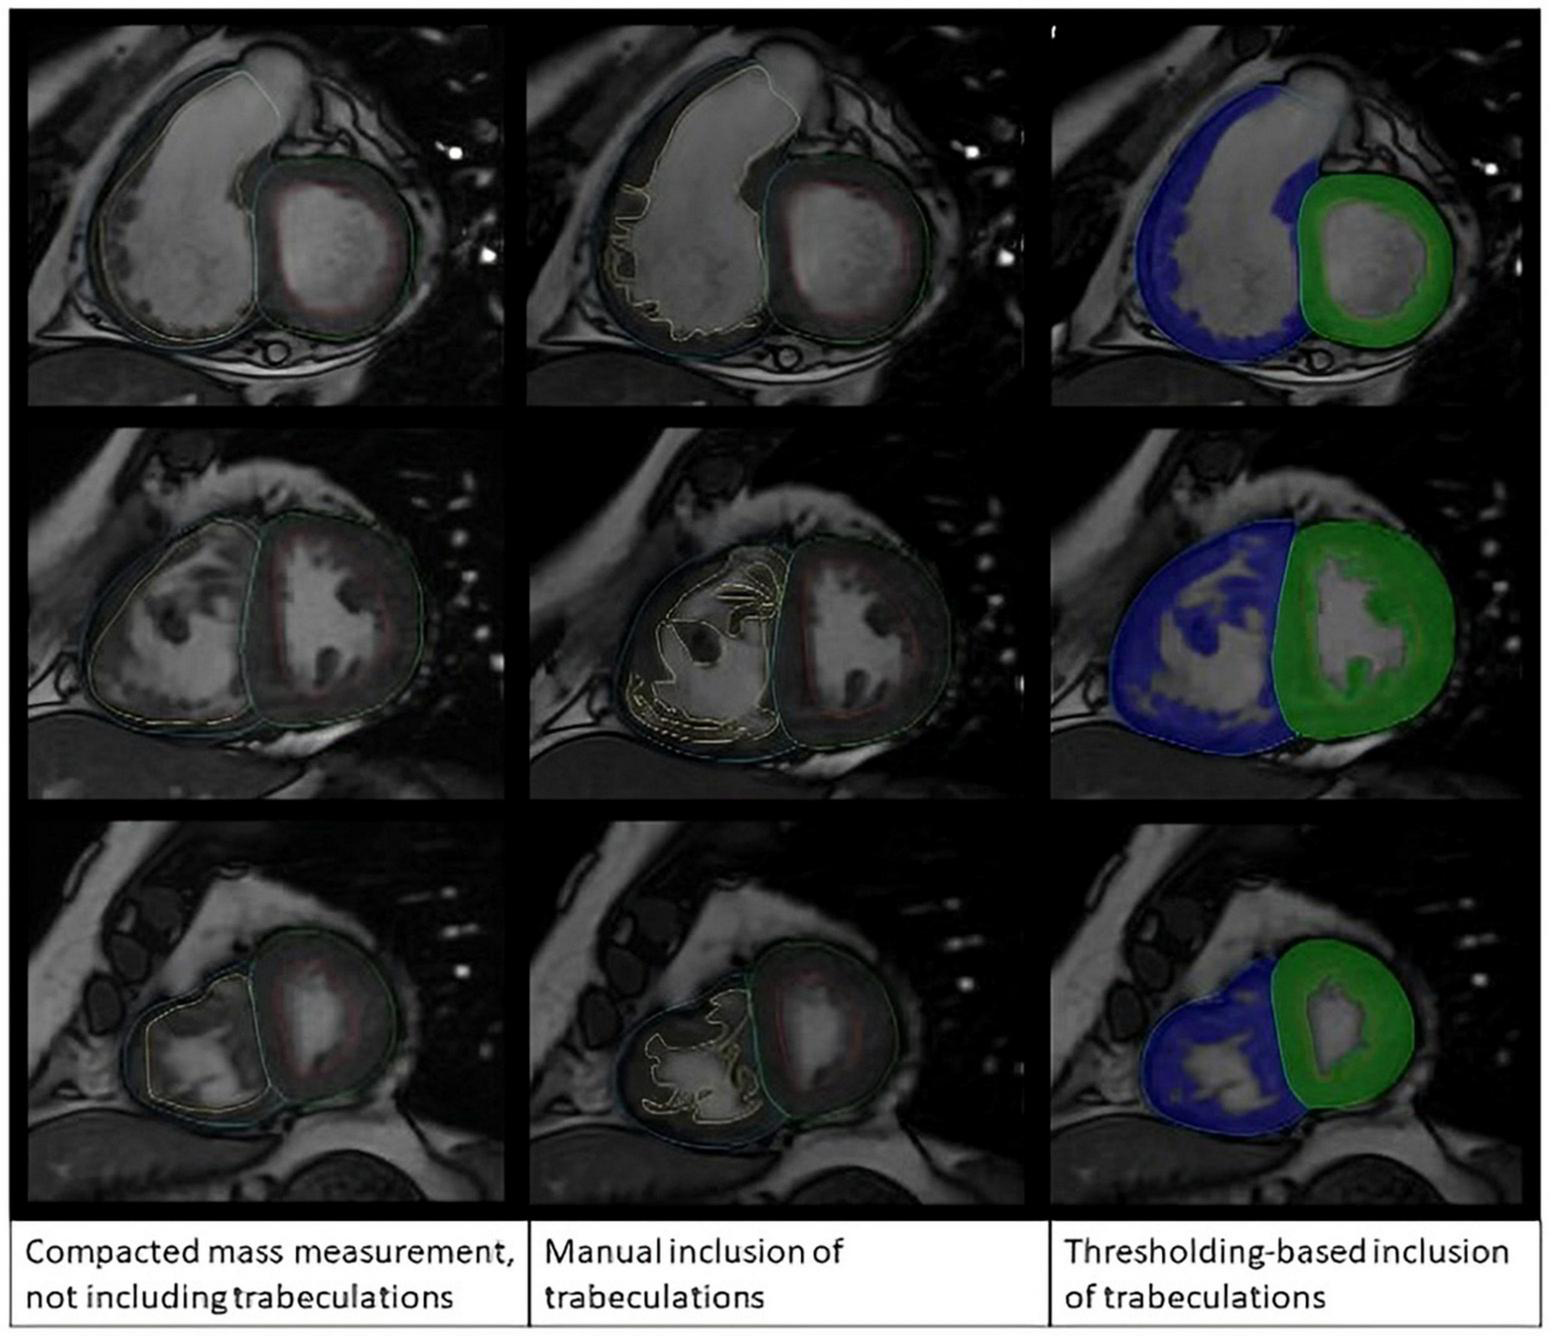

In the reproducibility assessment, analyses were performed by two operators trained on Qmass (AS and AMac had 12 and 1 year of experience in CMR, respectively). For the manual RV and LV mass analysis, the myocardium was contoured to include the trabeculation as muscle mass based on visual assessment of low pixel intensity areas in the blood pool (Figure 2). In the threshold technique, the endocardial contour was placed at the compacted endocardial surface, and the MassK threshold tool was selected. RV Myocardial mass including trabeculations was labeled a total mass, while myocardial mass excluding trabeculations was labeled compacted mass. Finally, trabeculation alone was labeled trabecula mass.

FIGURE 2

Manual tracing method compared with semi-automatic thresholding method.